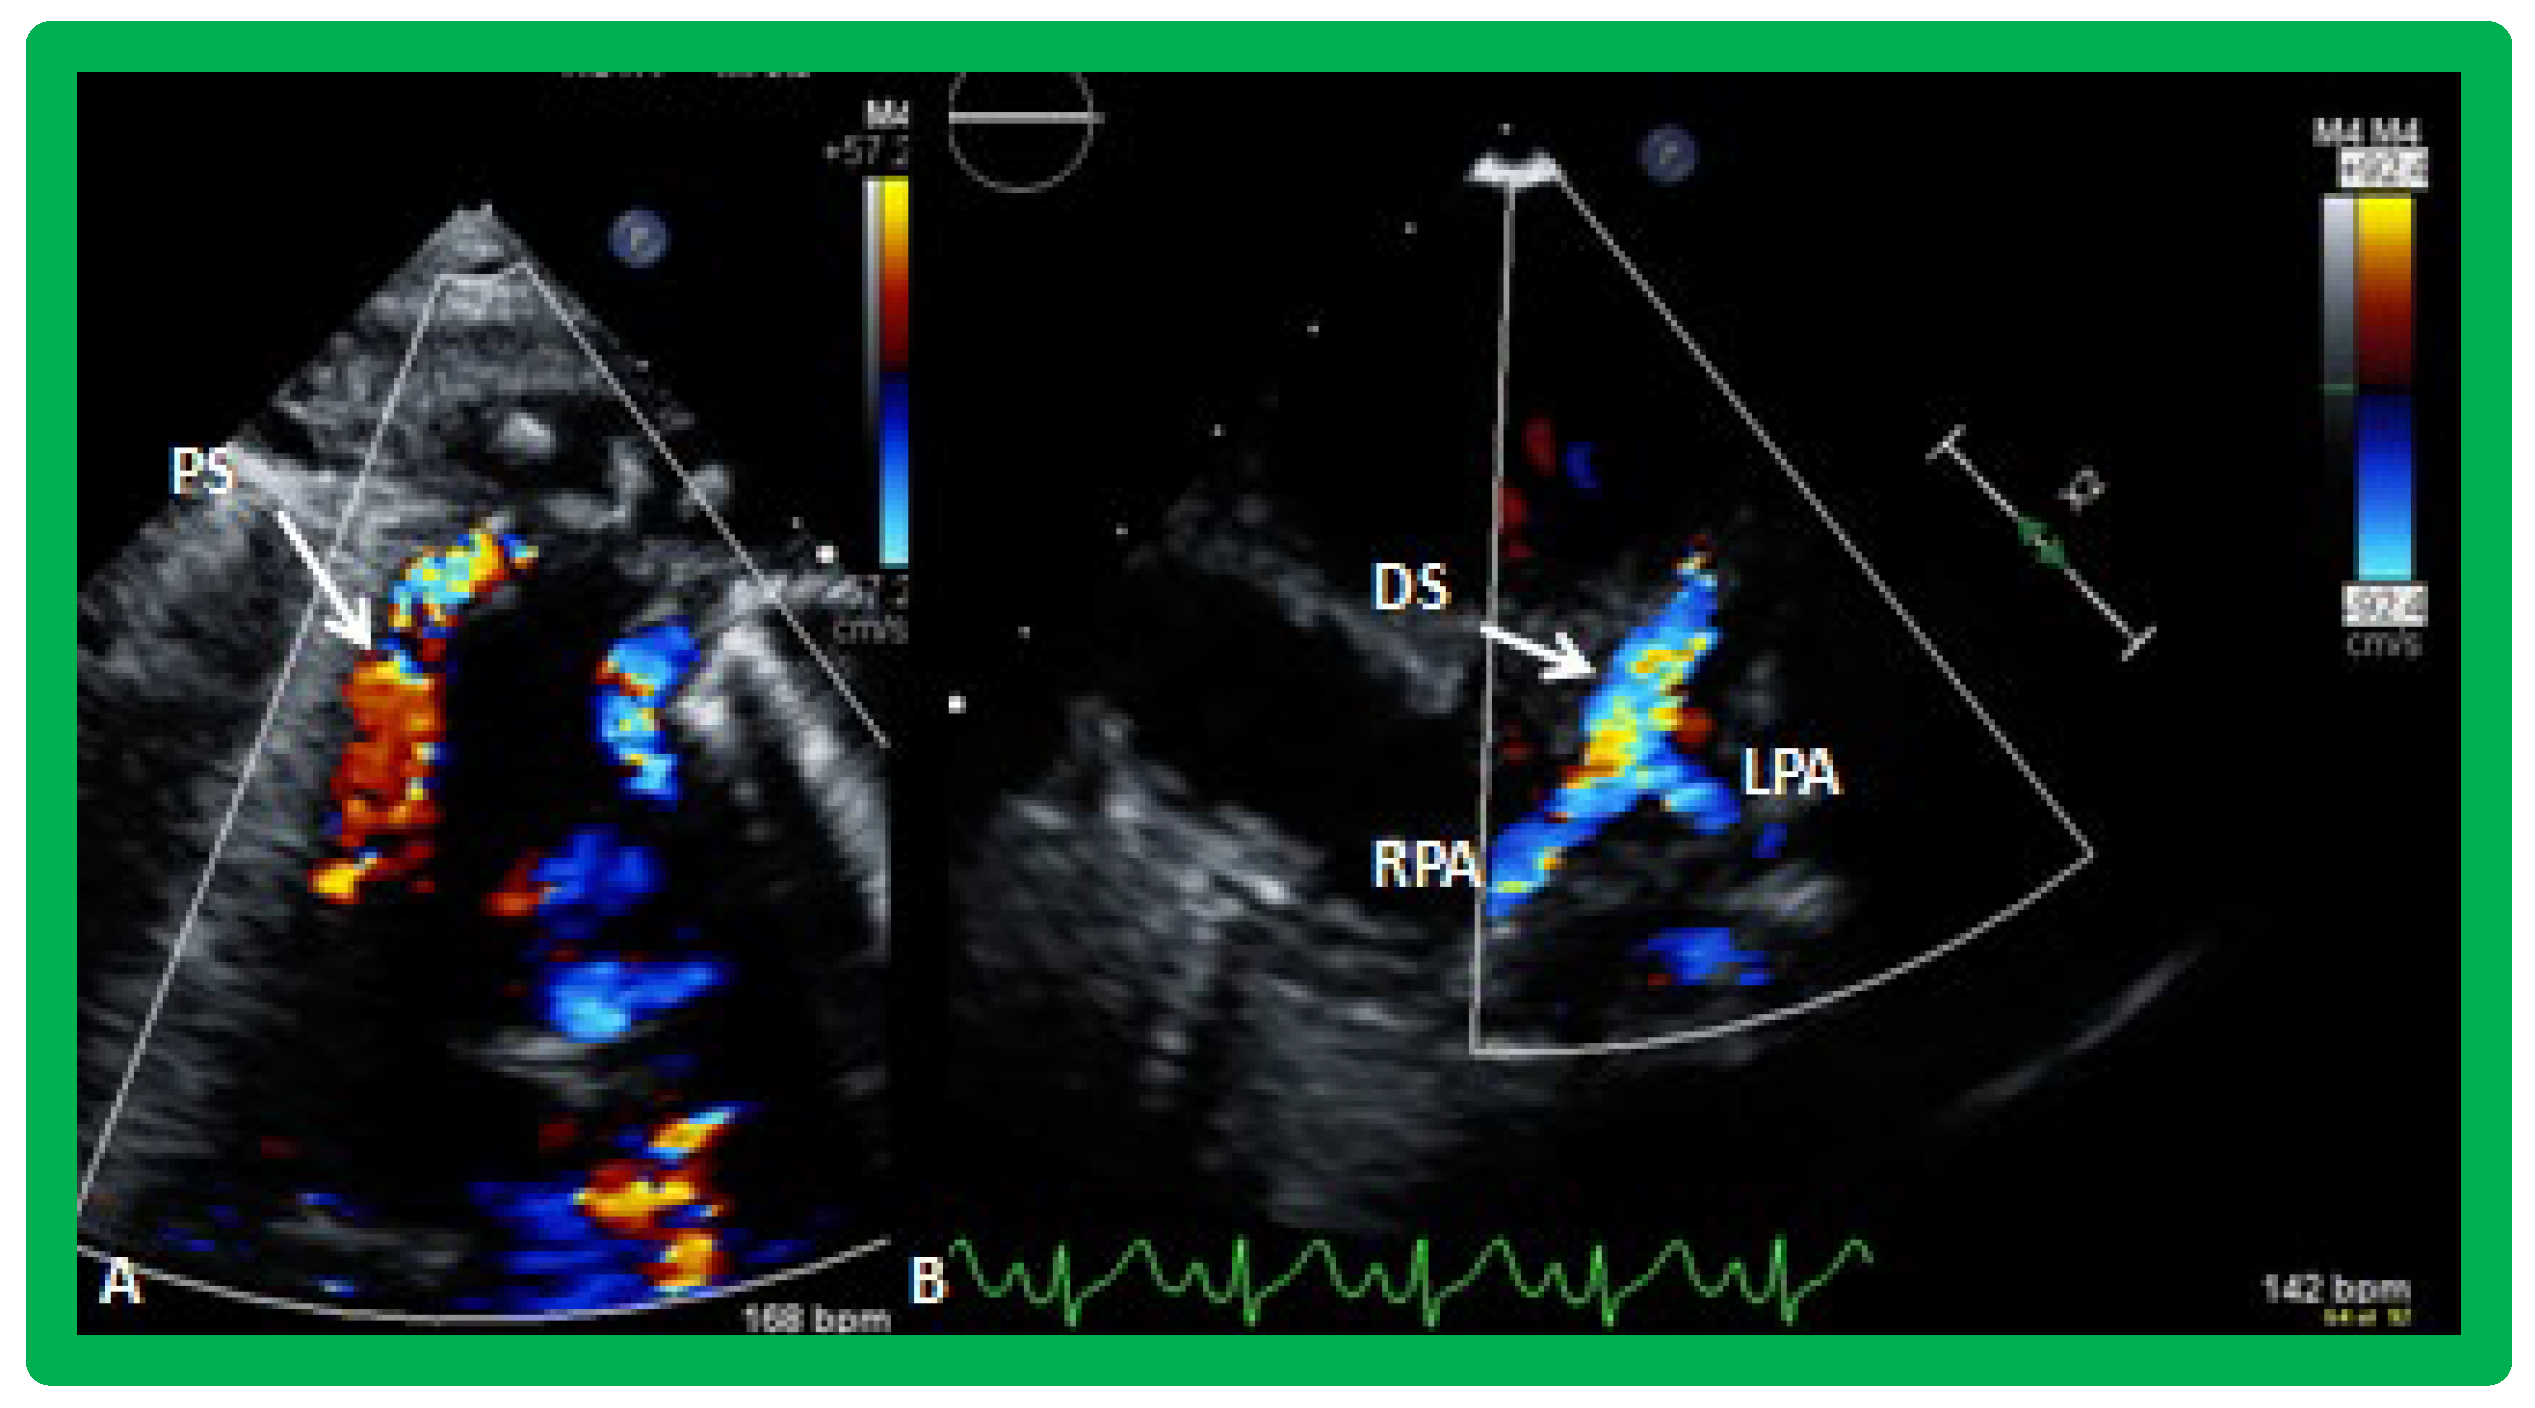

Figure 34. Selected video frames from parasternal short axis view demonstrating stenosis of the right pulmonary artery (RPA) by two dimensional (A) and color (B) and pulsed (C) Doppler imaging. Doppler calculated gradient was 18 mmHg (C). Ao, aorta.

Figure 35. Selected video frames from parasternal short axis view demonstrating hypoplsia of the right pulmonary artery (RPA) in two dimensional (A,B) and color flow (C) images. The measurements of the RPA (A) and left pulmonary artery (LPA) (B) are shown. Ao, aorta; MPA, main pulmonary artery.

Distortion or stenosis of the branch PAs may be secondary to palliative procedures performed at the time of initial presentation or may have developed spontaneously in the innate branch PAs. The careful 2D and Doppler interrogation of PAs should be undertaken to detect significant stenosis (Figure 34) or hypoplasia (Figure 35) and, if present, balloon angioplasty, stent implantation or surgery as deemed appropriate should be undertaken [38].